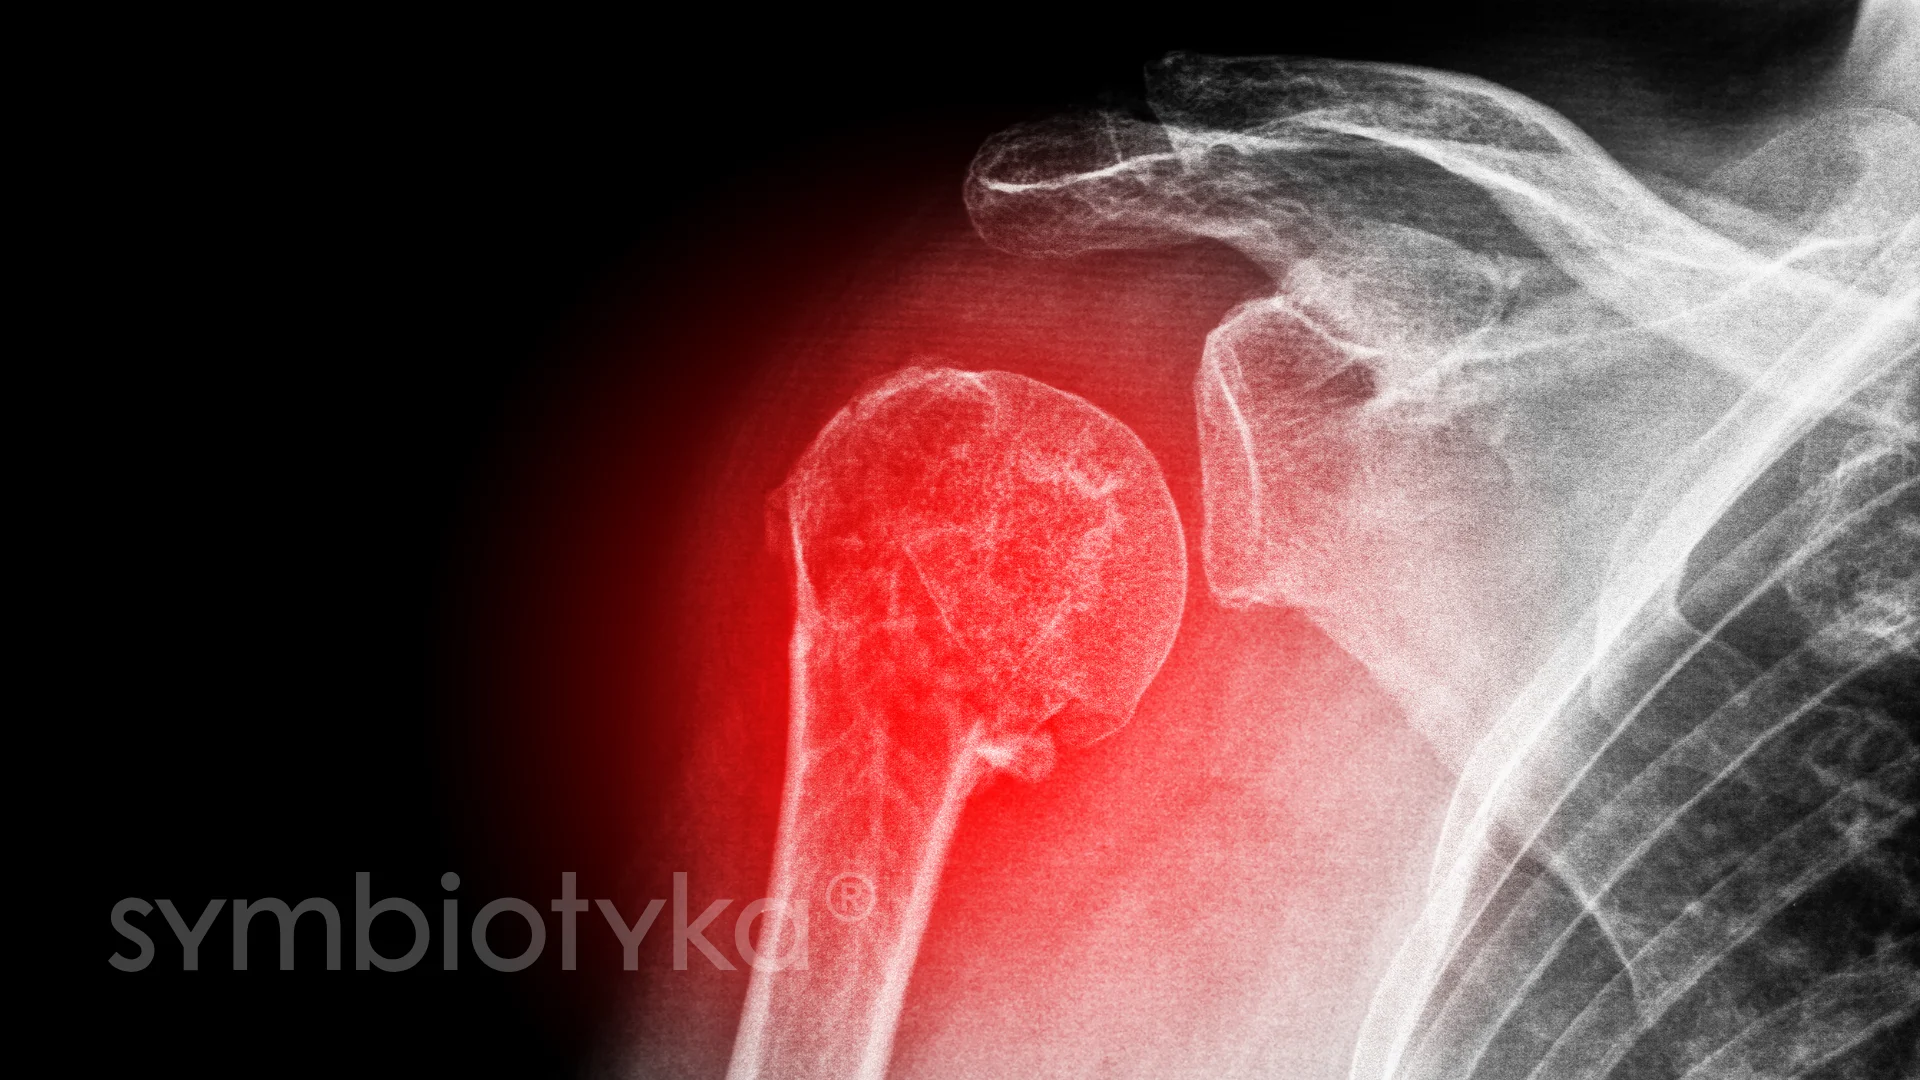

Плечовий суглоб є одним із найрухливіших у людському тілі. Він відповідає за широкий спектр рухів. Проте травми, вікові зміни, запальні процеси чи хронічні захворювання можуть поступово руйнувати його структури.

Плечовий суглоб є одним із найбільш рухливих у людському організмі, тому він постійно піддається високим навантаженням. З часом або під впливом зовнішніх факторів його структура може пошкоджуватися, що призводить до болю, обмеження рухливості та потреби у лікуванні.